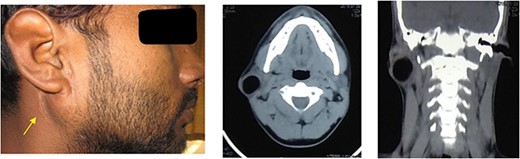

A 23-year-old male presented to the outpatient department with complaints of painless swelling below the right ear, which had been gradually progressing for 8 years. There was a history of similar swelling 9 years back, for which he underwent cyst excision, and the histopathology report was suggestive of a dermoid cyst. On examination, there was a single, mobile swelling of size 3 × 2 cm, with a smooth surface and soft consistency near the angle of the mandible. Scar from the previous surgery was visible over the swelling (Fig. 1). There was no palpable lymphadenopathy or any neurological deficit. Ultrasonography showed an enlarged right parotid gland, homogeneous in echotexture with a well-defined cystic lesion measuring 31 × 22 × 25 mm (volume 9 cc), with internal echoes in the superficial parotid gland. Fine needle aspiration cytology revealed proteinaceous background along with sparse histiocytes, lymphocytes and adipocyte clusters suggestive of a cystic lesion. Computed tomography (CT) scan revealed a well-defined cystic lesion measuring 21 × 23 mm in size in the right parotid gland with areas of fat attenuation (Fig. 1). Based on the history and investigations, this was suspected to be a case of recurrence of the dermoid cyst and the patient was planned for superficial parotidectomy.

Clinical picture of patient showing swelling in the right parotid region with visible scar and axial and coronal section of CT imaging showing well-defined cystic lesions in the right parotid gland.